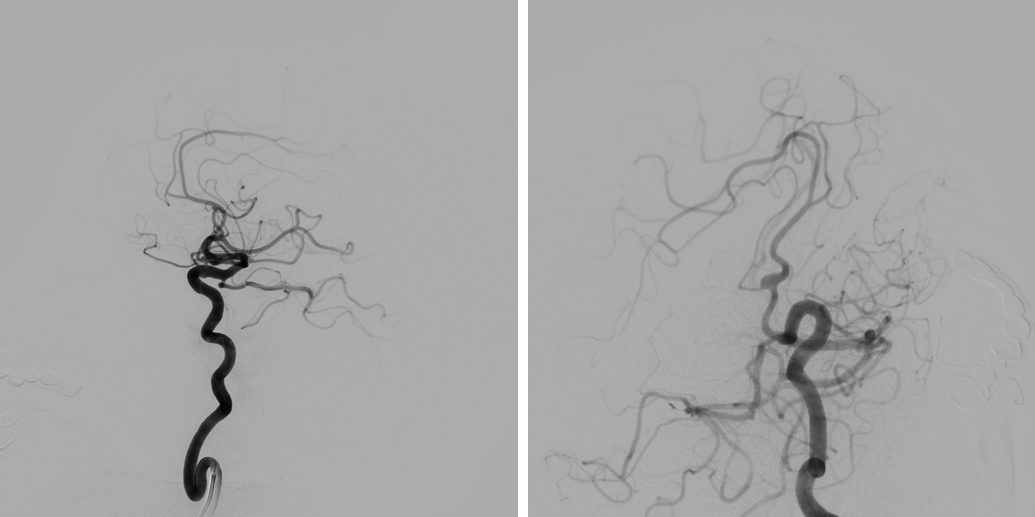

考虑到李女士动脉瘤基底极宽,必须支架辅助,为了降低其复发率,罗俊杰团队决定使用释放难度较大的编织支架。由于常年罹患高血压,李女士的颈内血管迂曲极为严重,血管最粗处不到2毫米,通往载瘤血管的“必经之路”上有连续两个180°的大转弯,要将直径0.5毫米左右的管道穿过“重重叠嶂”送至栓塞处。

血管造影显示,李女士的血管异常迂曲。

术中第一次微导管顺利到位后,释放支架时因血管迂曲,系统支撑不足,微导管滑落。